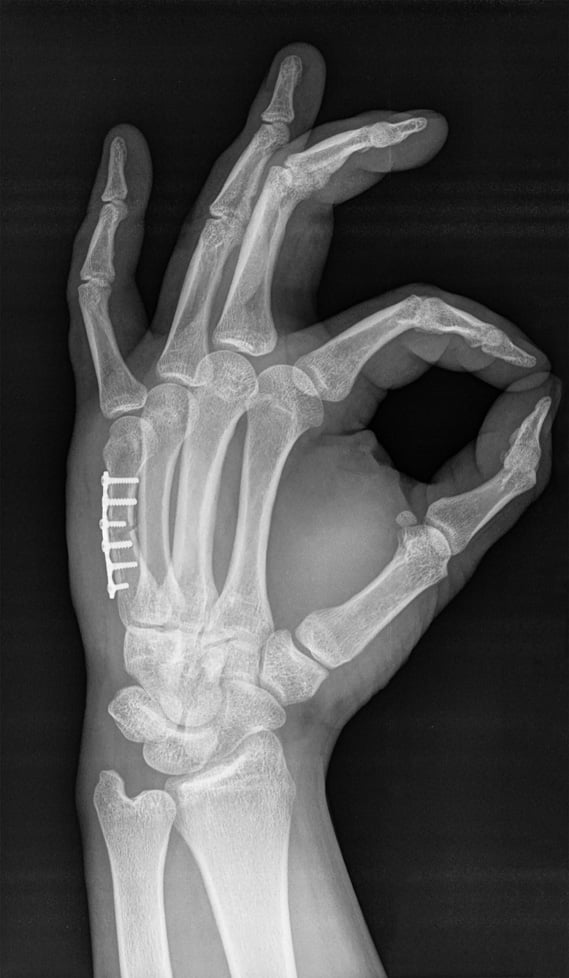

X-ray showing plating to repair a Metacarpal Fracture

Operative treatment: Surgical repair of metacarpal fractures is required when the fracture pieces are unstable (won’t stay in place), or not healing properly with cast treatment. We perform a regional block to numb the arm, and if the metacarpal can be set straight, we place metal wires through the skin and into the bone to keep it straight while it is healing. If the fracture is severe, we may need to make a small incision over the back of the hand to restore the alignment of the broken metacarpal directly and hold the pieces in place with tiny metal plate and screws. Sometimes, a second surgery is performed after the bone has healed to remove the plate and screws if they are uncomfortable under the skin or cause stiffness.